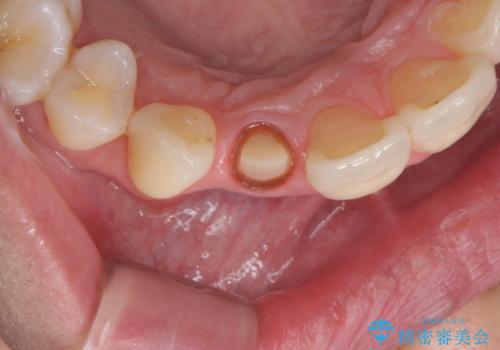

- 右上前歯の形と色が気になるとのことで来院された患者様です。

残っている歯に亀裂が多く走っていたため、クラウンでの修復処置を行います。

歯ぐきの扱いに気を付けることで、術前よりも歯ぐきの位置が改善されました。